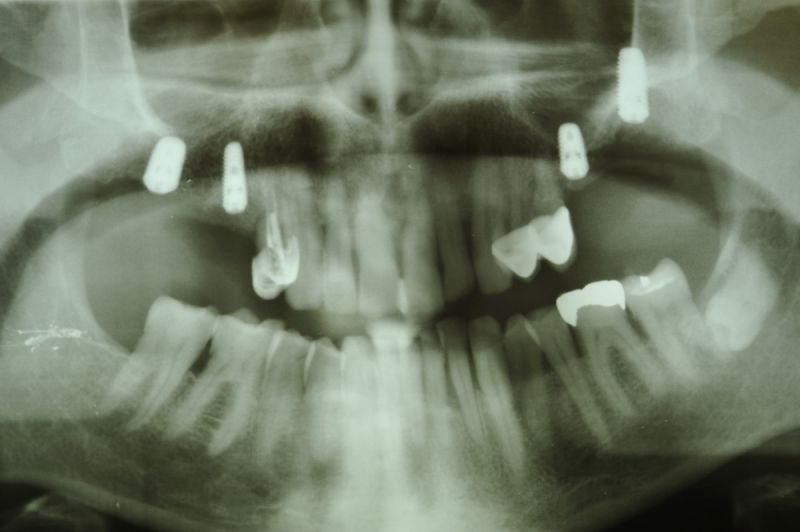

73 jähriger CMD-Patient im Recall

Der Patient hat vor 5 Jahren eine äußerst umfangreiche und komplexe CMD-Behandlung abgesclossen und befindet sich seitdem in einem engmaschigen vierteljährlichen Recall!

Seit 5 Jahren ist der Zustand des Patienten vollkommen unverändert!

Die aktuellen Taschentiefen liegen bei 2 Millimeter! Auch im Bereich der Implantate!

Auch in diesem Fall zeigt sich, dass es gerade bei älteren Patienten sinnvoll ist umfangreiche, festsitzende Versorgungen umzusetzen, so lange sich der Patient noch in einer gesundheitlich guten Konstitution befindet, um dann für die kommenden Lebensjahre Substanz vorzufinden, mit der man "arbeiten" kann.

Das Allerwichtigste bleibt aber der engmaschige, vierteljähliche Recall, der aus mehr besteht, als nur einem Zahnsteinentfernen! Wichtig ist die fortlaufende Dokumentation der verschiedenen Parameter der parodontalen Gesundheit und genauso wichtig eine Röntgenkontrolle etwas alle ein bis eineinhalb Jahre.